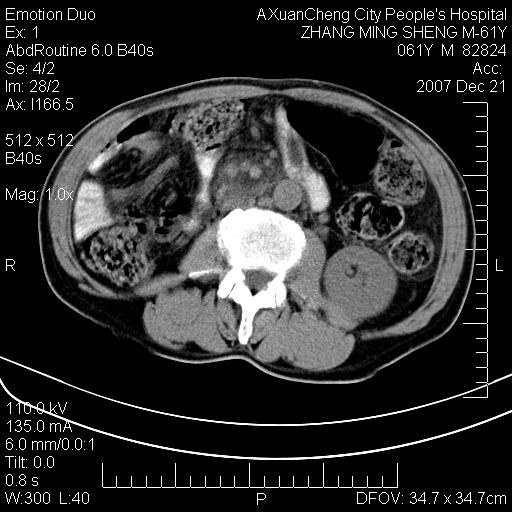

标题: CT11031:M61Y,胰腺占位 [打印本页]

标题: CT11031:M61Y,胰腺占位

大家侃侃门静脉和胆管系统怎么回事,肝内转移?

2,肝内多发结节状低密度占位,伴门脉及肠系膜上v栓子形成.考虑a;门脉及肠系膜上v血栓后肝改变.b;弥漫型肝癌伴门脉及肠系膜癌栓.

肝硬化,门脉高压,脾肿大;弥漫性肝癌,肝内、门脉、腹膜后淋巴结转移,肝内外胆管扩张,胰头区占位,建议mr检查

胰腺癌伴肝内转移;门脉、肠系膜上v癌栓形成。

考虑为:胰腺癌伴肝脏转移、腹膜后淋巴结转移,门静脉及肠系膜上静脉瘤栓形成。

胰体尾癌伴肝内转移,门静脉及肠系膜上静脉瘤栓形成.